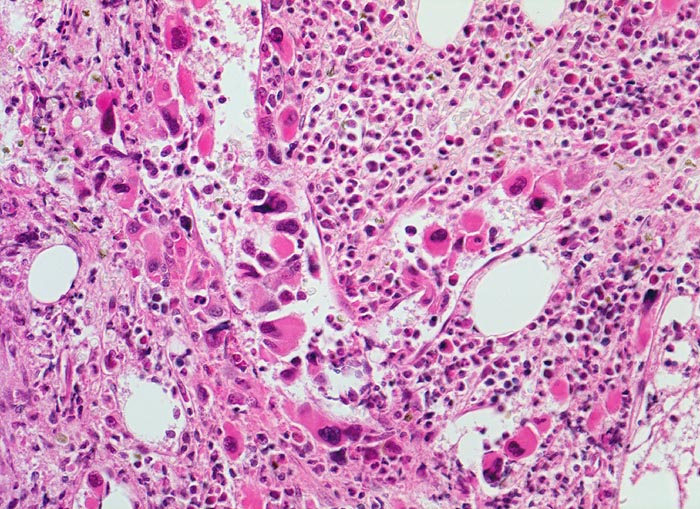

Primäre Myelofibrose (PMF)

Knochenmark, Beckenkamm

Vermehrung von atypischen, in Gruppen liegenden Megakaryozyten mit hypolobierten Kernen. Teils nacktkernige Megakaryozyten (d.h. praktisch ohne Zytoplasma). Die Megakaryozyten liegen in einem dilatierten Sinusoid bzw. unmittelbar daneben. Hyperplasie von ausreifenden Granulozyten. Erythropoese hypoplastisch. Durch die Fibrose entsteht der Eindruck von strömenden Zellen (links im Bild).

Splenomegalie, leichte Anämie, Leukozytose und Thrombozytose festgestellt bei einer Routineuntersuchung bei abgesehen von leichter Müdigkeit asymptomatischer Patientin.

Histologie

200